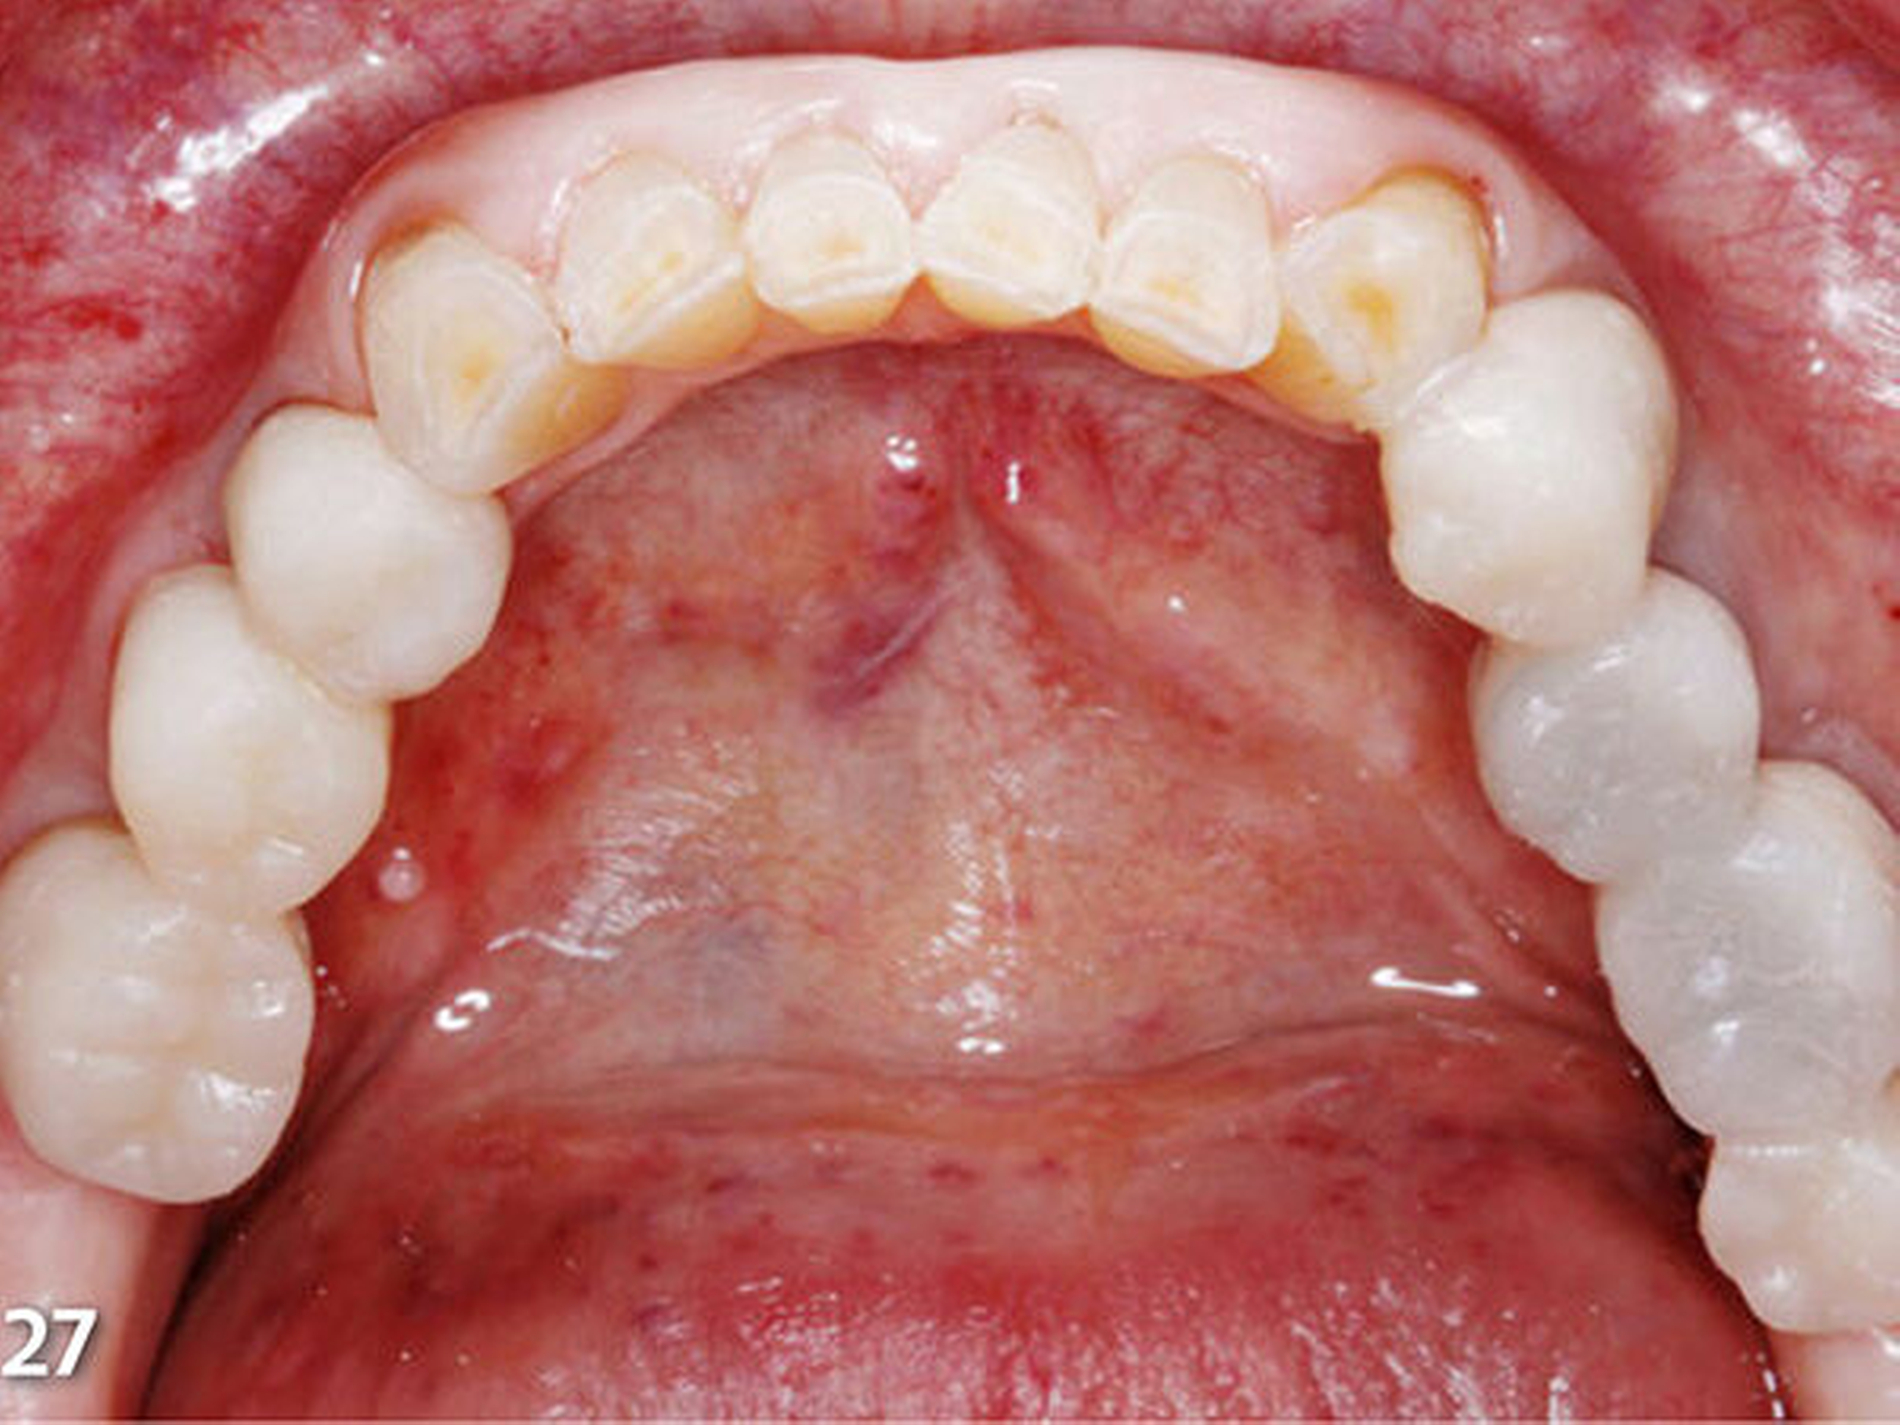

Analog erfolgte der Aufbau der Seitenzahnkauflächen der anderen Kieferhälfte ebenfalls in zwei Schritten (Abb.27). Durch den Aufbau aller Seitenzähne des Unterkiefers ist die temporäre Bisshebung bereits weitgehend abgeschlossen (Abb.28). Mit der dritten Übertragungsschiene (Schiene 3) (Abb.29) wurden die Unterkieferfrontzähne nach Ätzung der Zahnhartsubstanzen mit Phosphorsäure und nachfolgender adhäsiver Vorbehandlung inzisal aufgebaut (Abb.30).